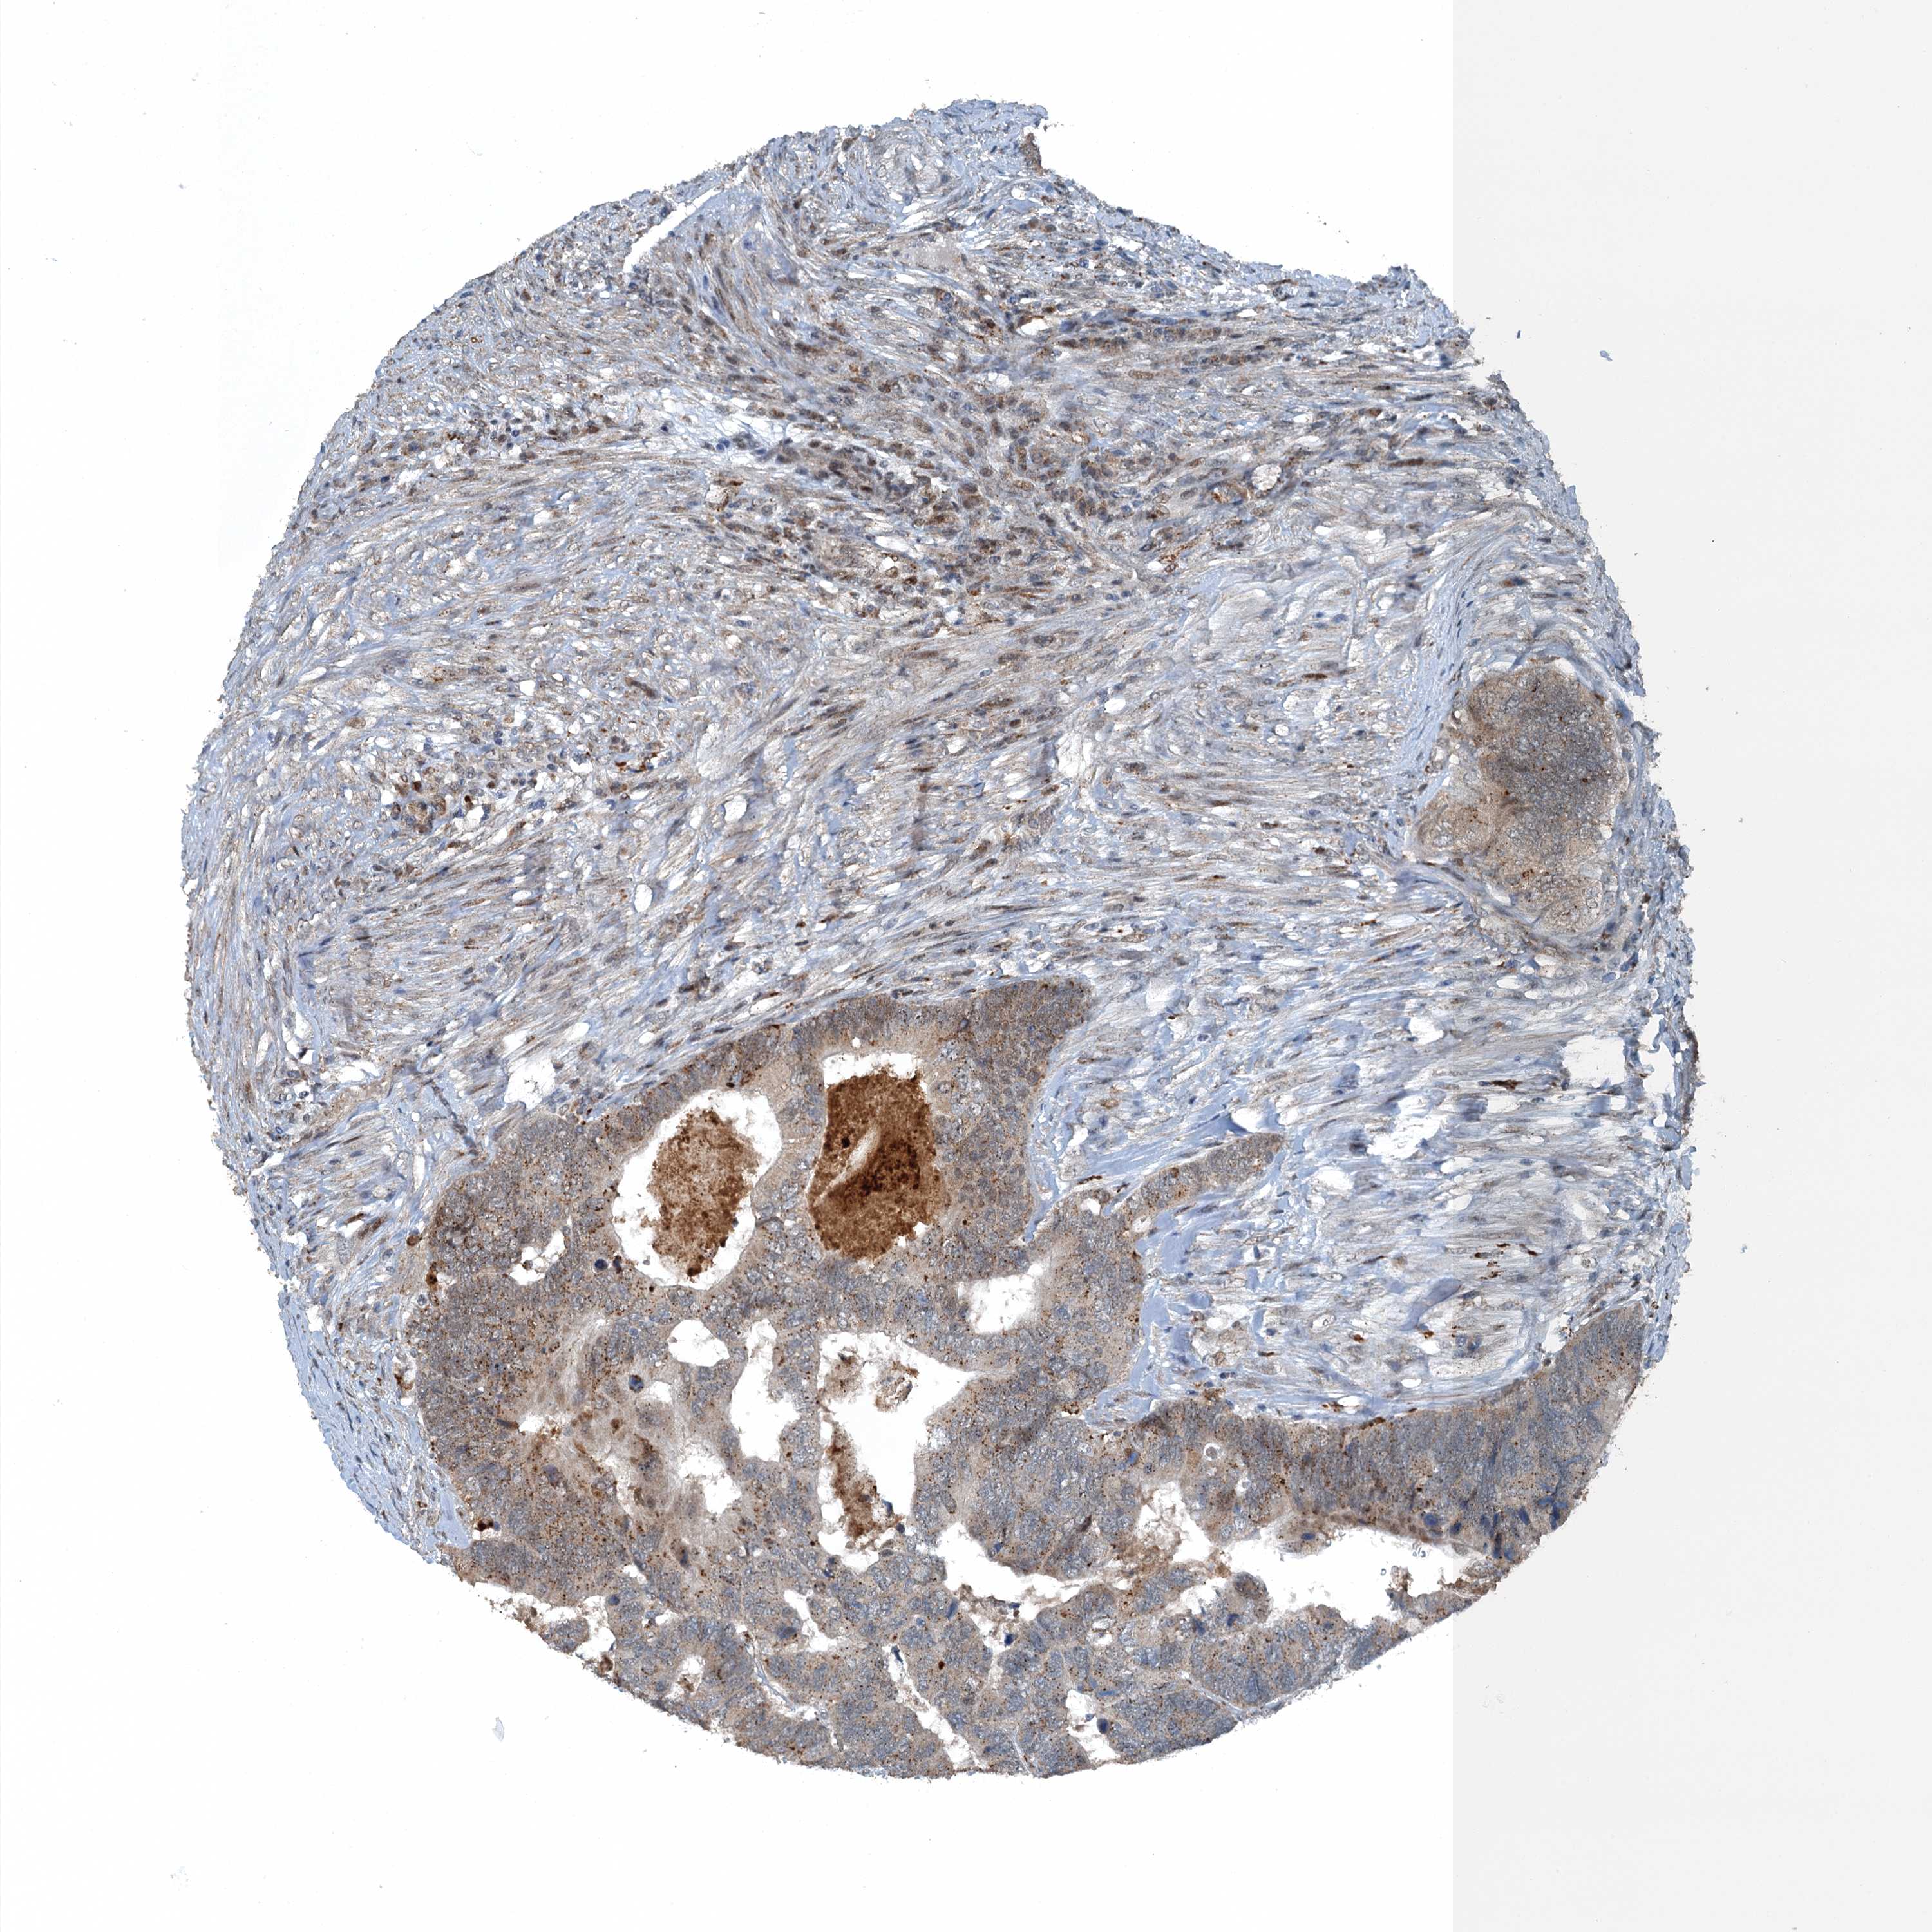

Colorectal cancer

Human cancer

Colon adenocarcinoma